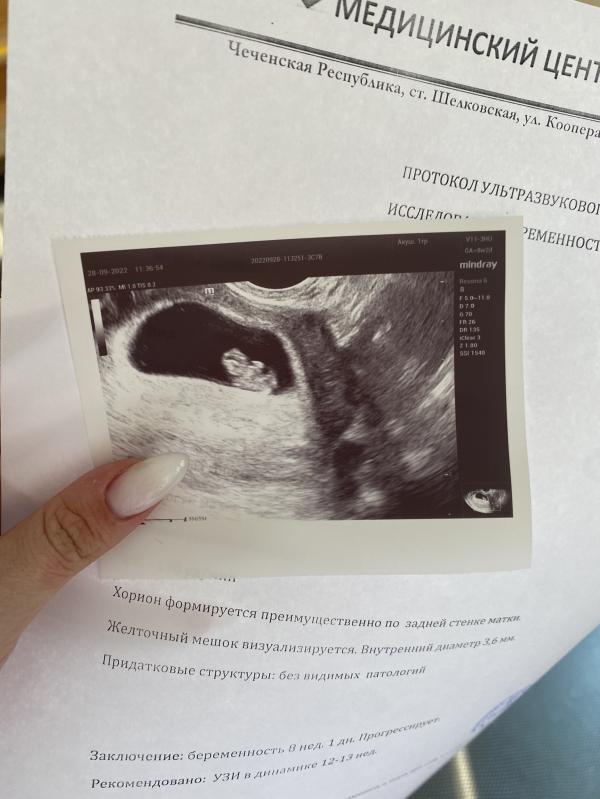

По акушерскому сроку 8.2, по узи 8.1 недель ☀️

Сердцебиение отличное - 178 🥳

Выросли в 3 раза, уже появляются ручки и ножки ⭐️